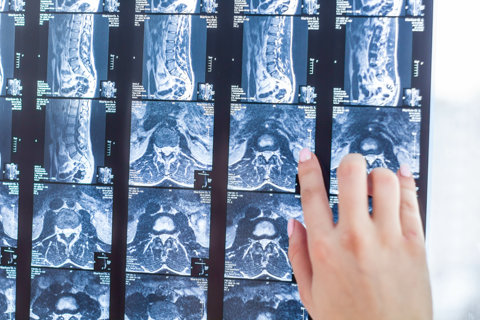

Over the next day, she began to pass urine more frequently than usual and the numbness was radiating to her right side. She booked an appointment with her GP, who immediately referred her back to the A&E department of the Defendant hospital with suspected Cauda Equina Syndrome. She underwent an MRI scan which confirmed the Cauda Equina Syndrome diagnosis, before undergoing an emergency operation.